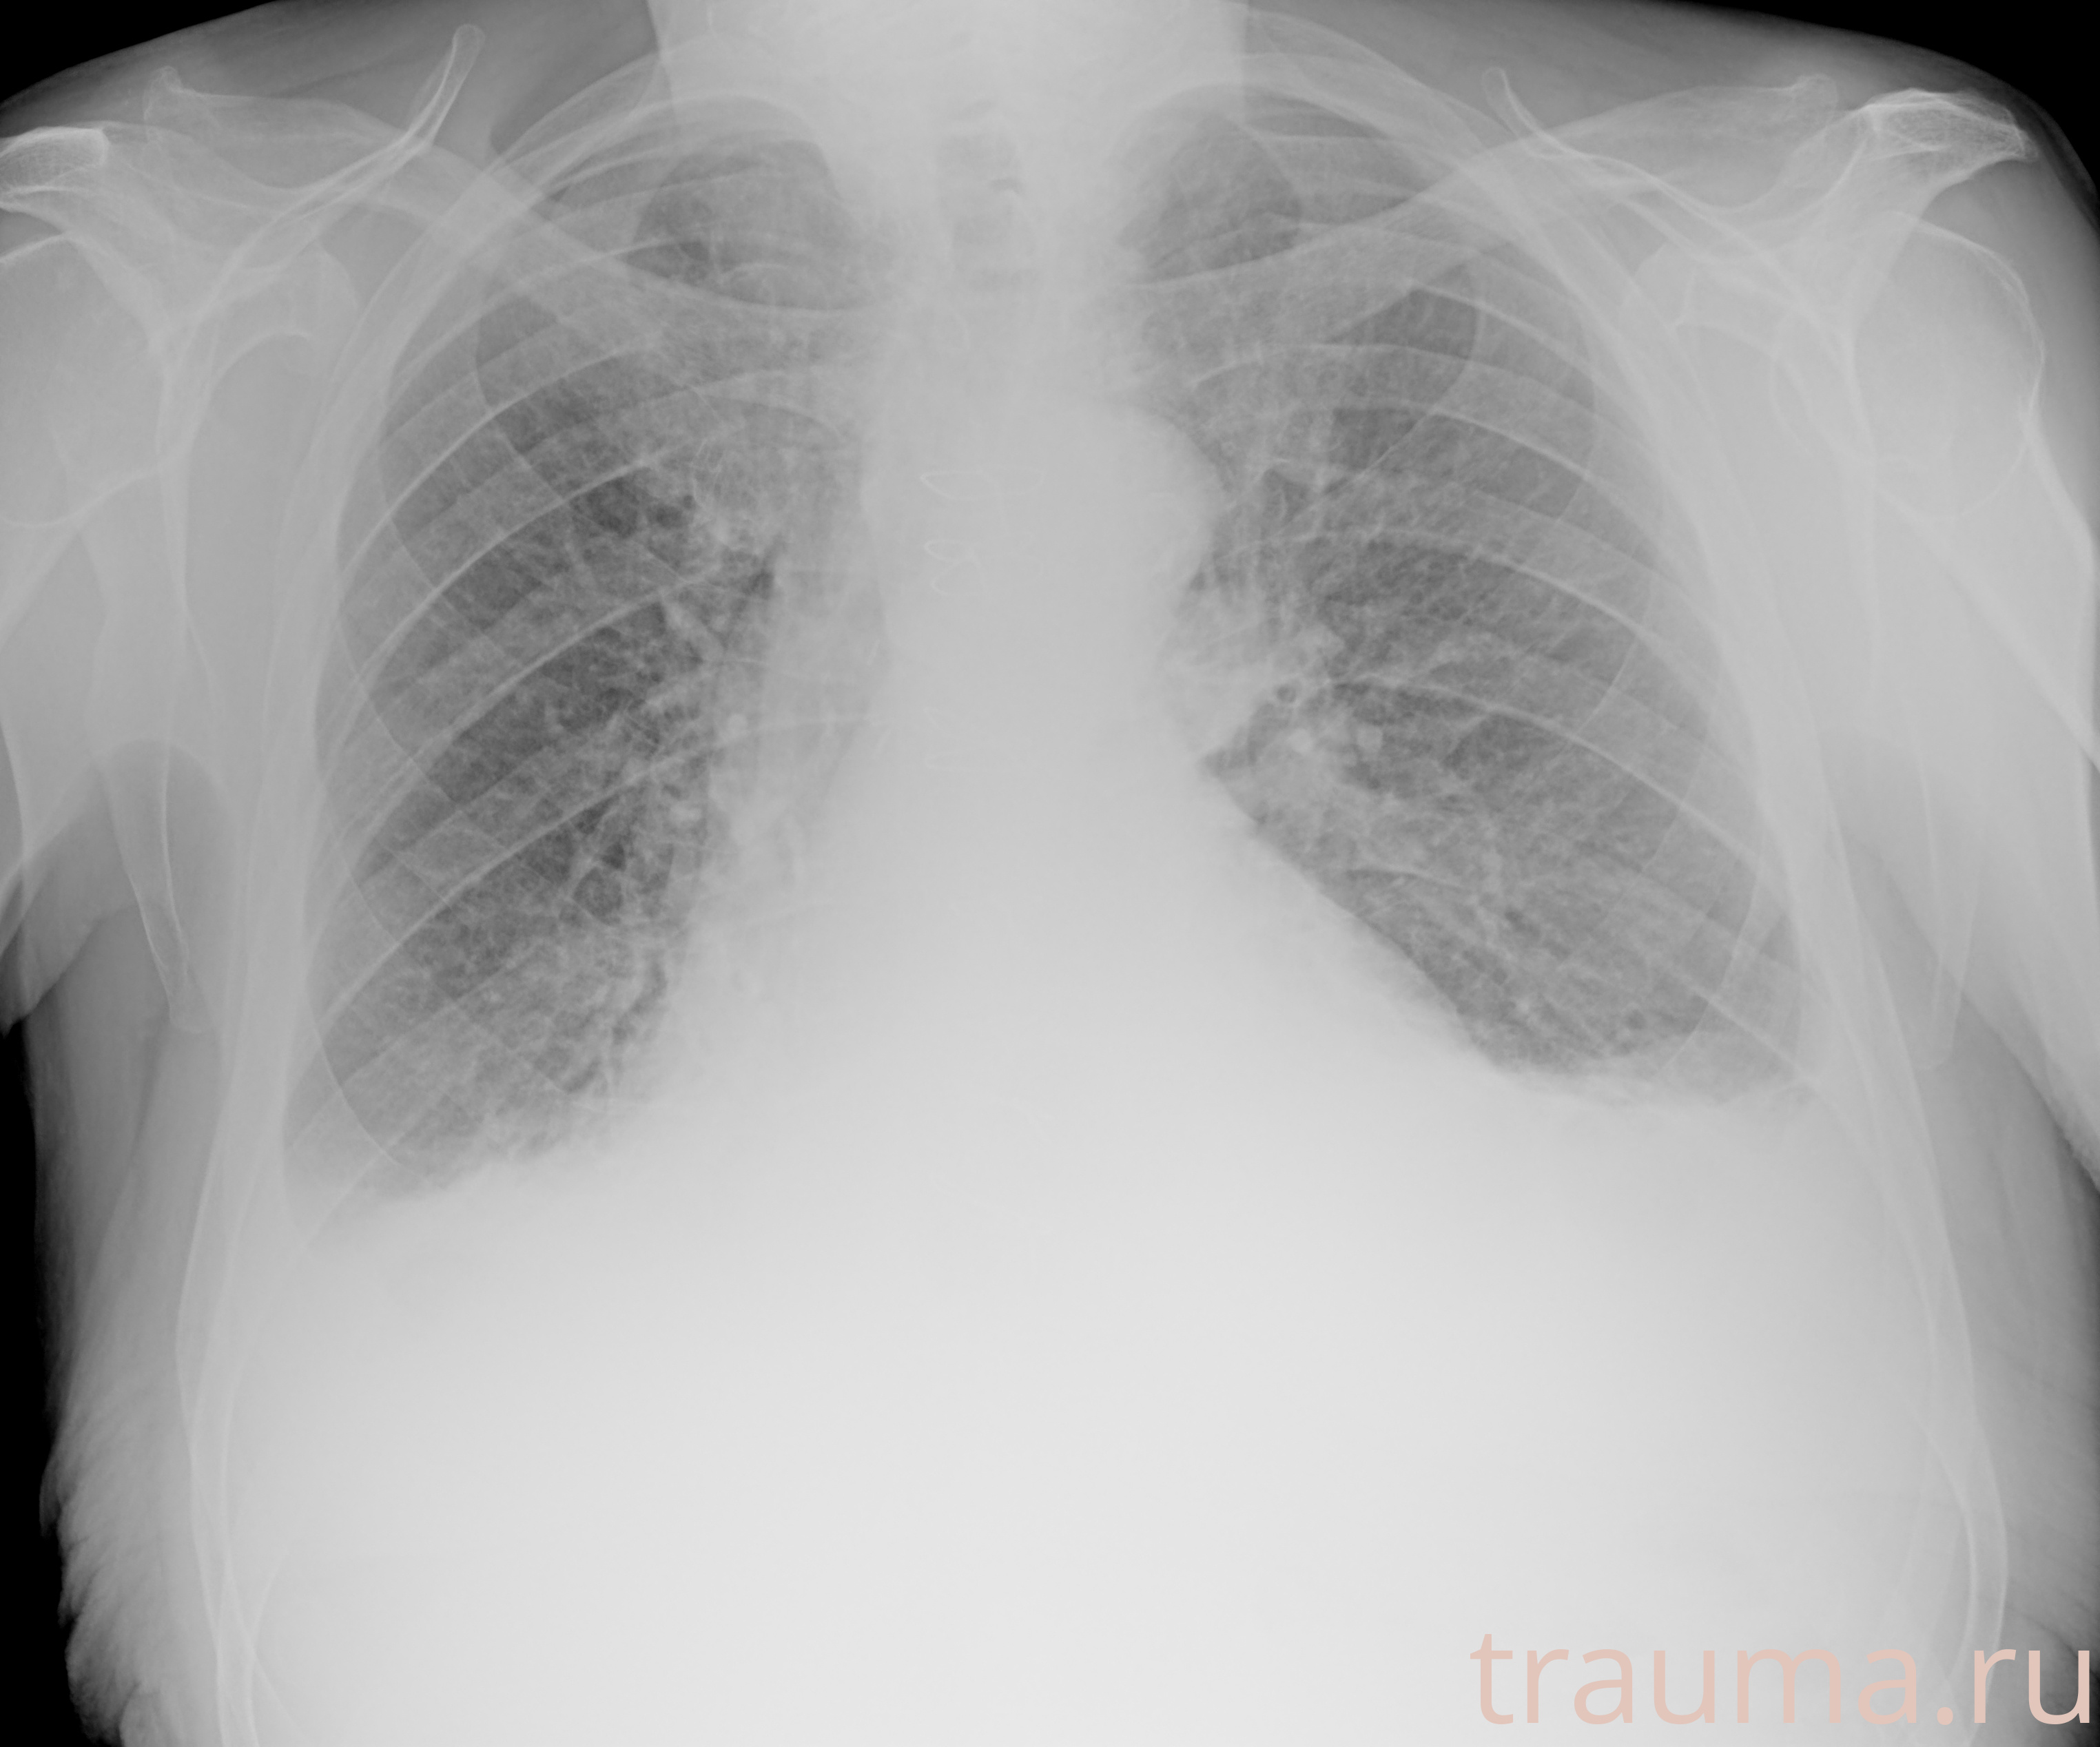

Рентгенограммы

Рентген на дому: по вашему адресу приезжает врач-рентгенолог, травматолог-ортопед с мобильным рентгеновским аппаратом, проводит диагностику травмы или заболевания, делает необходимые рентгенограммы, дает рекомендации по дальнейшему лечению. Получить качественные снимки в домашних условиях возможно благодаря уникальной методике, разработанной МосРентген Центром для института  Склифосовского